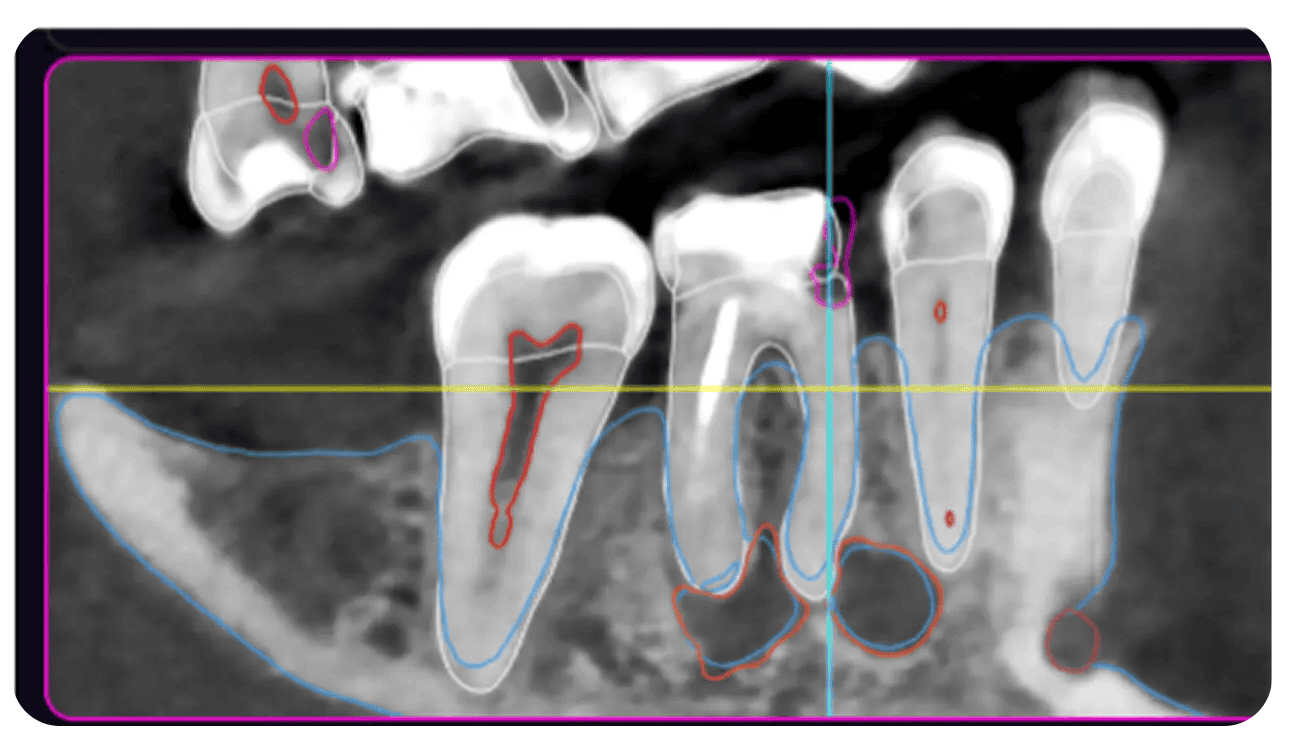

Raportul Modelului 3D de inteligență artificială include un mod de reconstrucție în mai multe planuri. Secțiunile sunt poziționate în funcție de obiectul selectat în vizualizarea 3D și prezintă contururi colorate ale structurilor segmentate.

Contururi colorate ale structurilor segmentate în reconstrucția multiplanară (MPR)

Trasarea automată a canalului mandibular